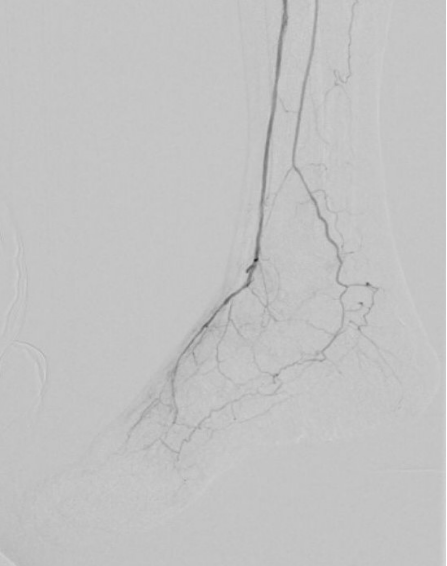

1. 术前造影:

2. 经鞘置入椎管、CXI、V18导丝正向开通股浅动脉下段,导丝通过,导管无法跟进,经皮穿刺钙化灶,导管跟进造影发现位于内膜下。

3. 经皮穿刺胫前动脉上段,置入新V18导丝,跟进CXI,与正向的椎管双向会师,建立导丝通路,予以3.0球囊预扩张。

4. 开通胫前-足背动脉